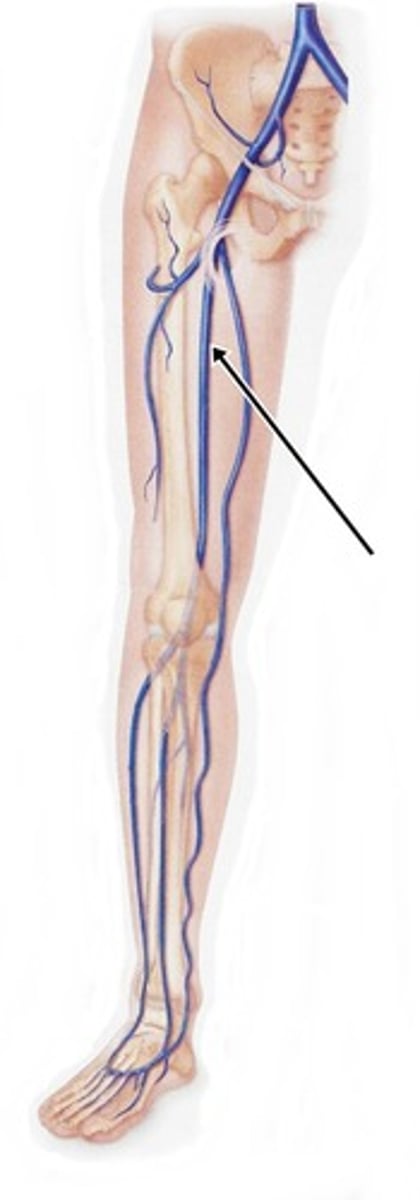

femoral vein

saphenous vein

popliteal vein

anterior tibial vein

posterior tibial vein